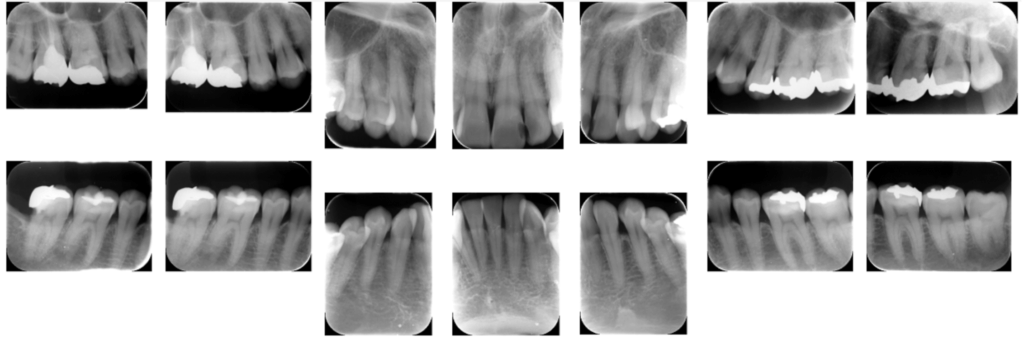

デンタルX線分析(歯の根の状態をチェック)

矯正治療では、見た目だけでなく歯の根(歯根)の状態を確認することも大切です。

そのため、当院では1本ずつの歯を丁寧に確認できるデンタルX線写真を撮影しています。

診断まとめ:5つのレベルでの評価

当院では、歯並びやかみ合わせを5つのレベルで評価しています。

これは、見た目だけでなく「どの程度のズレがあるのか」を客観的に把握するための独自チャートです。

この方の分析結果では、

歯並びの調和:特に上の歯でデコボコが多い

前突度:わずかに下顎が前に出ている

垂直度:かみ合わせが強い傾向あり

正中偏位:やや右側にずれている

プロフィール(横顔バランス):問題なし

このように、複数の項目を総合して診断を行い、

どの部分に調整が必要かを明確にしていきます。